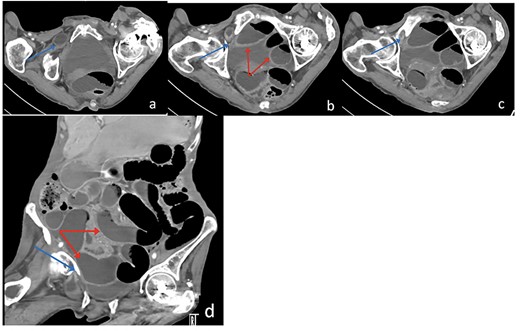

Due to the high-grade small bowel obstruction, the patient was pushed as an emergency case to the operating room. The surgery started and ended as a laparoscopic procedure with three small incisions; 12, 11 and 5 mm port sizes located supraumbilically, right and left midclavicular line relatively. Once the peritoneum was penetrated, and gas insufflated, diagnostic laparoscopy was done, and the obturator hernia with bowel content was visualized (Fig. 3), with a transitional zone at the hernia site showing a proximal dilatation and distal collapse of the small bowel. After that, reduction of the hernia content was subsequently made with no signs of gangrene or ischemia of the bowel. Then, the small bowel was run as a whole to eliminate any other transitional zones or pathology, which was unremarkable. Therefore, as there was no contamination, ischemia or perforation, a Vicryl mesh was elected and inserted as a plug into the obturator opening using a peritoneal flap and fixed (Fig. 4). Once the fixation was obtained, a ProGrip mesh was then applied to cover the whole right area (Fig. 5), which was covered by the peritoneum afterwards. The abdomen was inspected and the bowel looked healthy. Lastly, the ports were removed, the incisions were closed, the skin was clipped and then the dressing was applied.

An intraoperative figure of the Vicryl mesh plug inserted into the obturator opening.